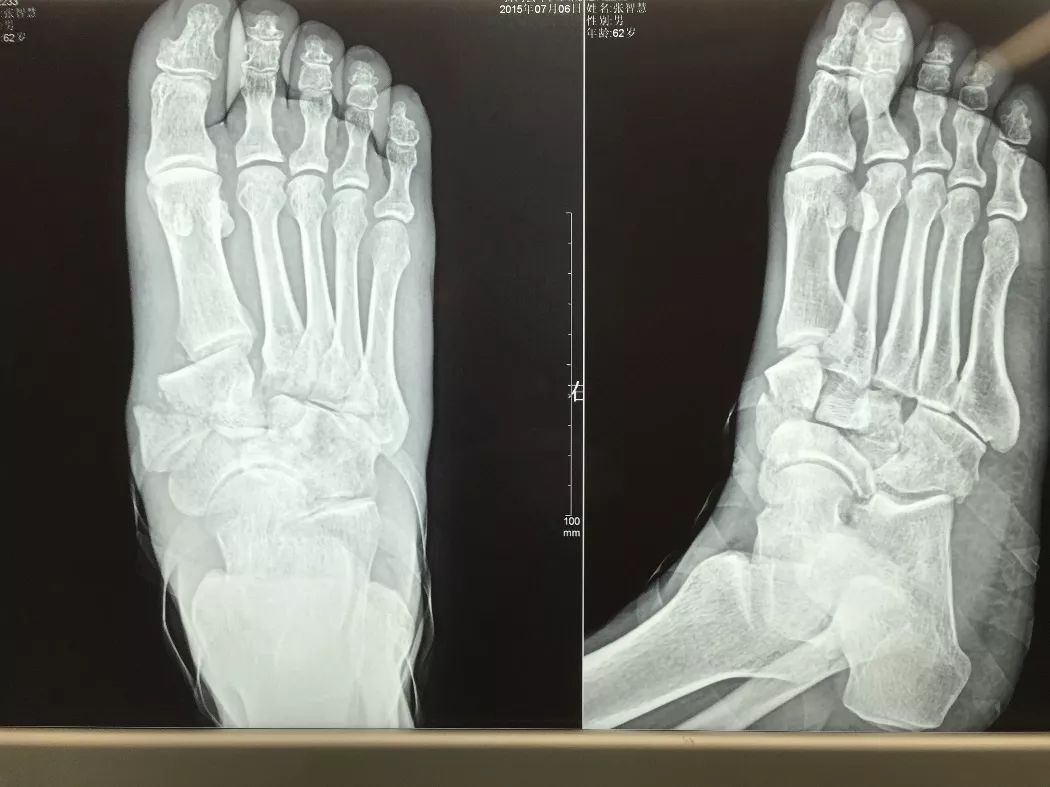

下面1例是我的学生所发。病史清楚,跗骨骨折后伤口开放,每次换药用双氧水冲洗伤口,造成骨坏死

跗骨感染

该例患者需要汲取的经验和教训:不要使用双氧水冲洗伤口死骨密度高是因为不参与代谢周围骨疏松治疗清理死骨后用骨水泥诱发诱导模反复几次做半开放植骨手术后走路刺激骨愈合,改善骨质愈合。